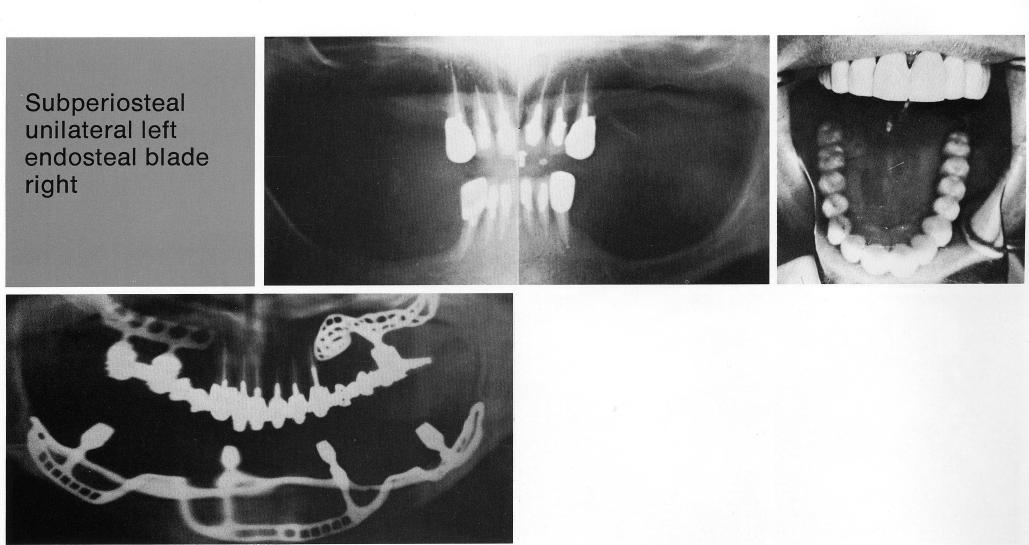

Subperiosteal unilateral left

endosteal blade

right

A full-arch restoration was used here, with natural teeth as anterior support. Posterior support was provided by bilateral implants, a subperiosteal implant on one side and a bladevent on the other.